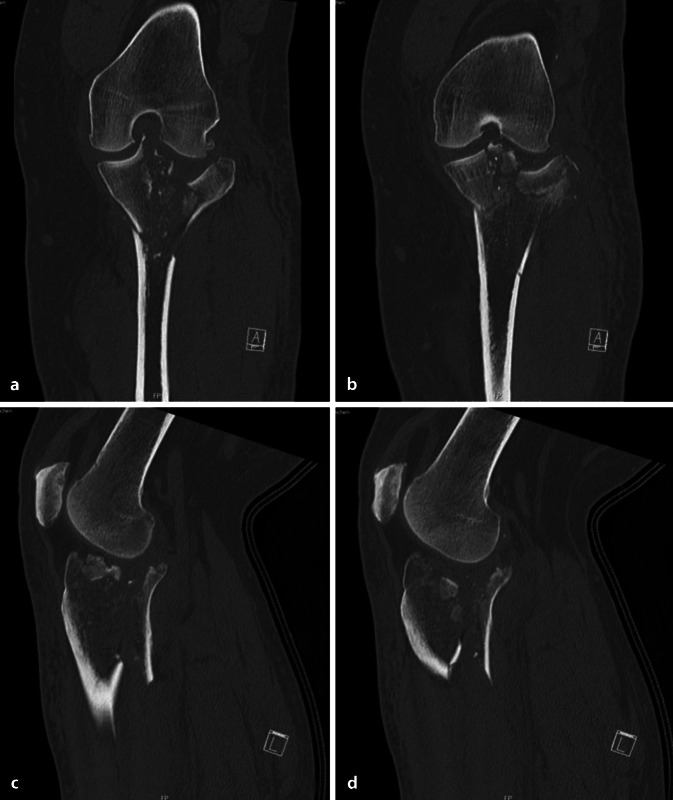

| Tibiakopffraktur Typ Schatzker VI (Abb. 4, 5) |

1. Anlage eines Fixateur externe 2. Plattenosteosynthese via dorsomedialem Zugang 3. Plattenosteosynthese via anterolateralem Zugang |